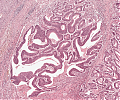

A69 Tubuläres Adenom (Kolon)

Nebeneinander normaler Kolondrüsen und adenomatöser Drüsen.

A69 Tubuläres Adenom (Kolon)

Tubuläre Drüsenbildung mit geringen Epithelatypien und einzelnen noch erhaltenen Becherzellen.